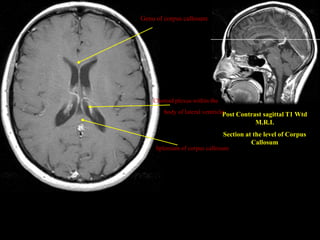

Genu of corpus callosum

Choroid plexus within the

body of lateral ventricle

Post Contrast sagittal T1 Wtd

M.R.I.

Section at the level of Corpus

Callosum

Splenium of corpus callosum

Genu of corpuscallosum Choroid plexus within the body of lateral ventricle Post Contrast sagittal T1 Wtd M.R.I. Section at the level of Corpus Callosum Splenium of corpus callosum